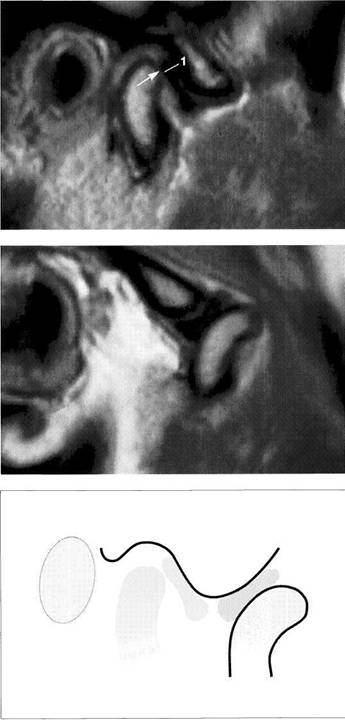

Normal joint

Left: Macroscopic anatomical pre­paration of a right temporo­mandibular joint with normal disk position. The pars posterior (1), pars anterior (2), pars media (arrow), and condyle (3) can be clearly seen.

Right: In spite of the reduction in signal caused by formalin fixation, the corresponding slice in MRI shows the identical relationships between the disk (1,2) and condyle

Medial disk displacement

Left: Formalin-fixed preparation from a right joint. In this anterosu-perior view, the displacement of the disk (arrows) toward the medial is evident.

Lateral pterygoid muscle

Lateral pole

Medial pole

Right: MRI in the angled coronal plane confirms the medial disk po­sition (arrows). The contours of the fossa and condyle are reproduced precisely.

Shape of the pars posterior

Left: Macroscopic anatomical pre­paration of a right articular disk showing its positional relationship to the condyle. The posteroinferior edge of the pars posterior (1) shows a small triangular area of fi­brosis (arrows).

Right: In spite of the sharply re­duced signal emission resulting from formalin fixation, even this type of change is accurately repro­duced (arrows). Here the use of a combination of T1 and T2 weight­ing is often helpful.

Reproduction of Anatomical Detail in MRI

Fibrosis of the bilaminar zone

Left: Formalin-fixed preparation of the centromedial part of a left tem­poromandibular joint with localized fibrosis of the bilaminar zone (ar­rows).

Pars posterior

Right: The MRI accurately repro­duces the abnormality (arrows) dis­tal to the flattened pars posterior. The contour of the condyle is indi­cated by a broken line.

Presumed "posterior disk displacement"

Left: Macroscopic preparation of a left temporomandibular joint with normal positioning of the pars an­terior (1) and pars posterior (2) in the lateral portion of the joint. The retrodiskal structures appear thick­ened.

Right: In an MRI there appears at first glance to be a posterior disk displacement (arrows). Under clos­er inspection, however, it can be seen that the pars anterior (1) and pars posterior (2) lie in correct rela­tion to the condyle.

Left: A view of the disk and the bil­aminar zone after further prepara­tion again reveals the correct posi­tional relationships. Here the pars anterior (1) and pars posterior (2) can be identified more readily. The presumed "posterior disk displace­ment" is a false positive interpreta­tion of the fibrosis of the bilaminar zone (arrows).

Right: MRI of the same joint shown in Figure 427.

Disk perforation and osteoarthrosis

Left: Anatomical preparation of a left temporomandibular joint with arthrotic changes (black arrows) and extensive disk perforation (white arrows). In the anterior re­gion only a part of the former pars anterior (1) can still be recognized.

Right: MRI shows similar conditions. The cortical layer of the arthrotic condyle is thickened extensively (arrows). The remainder of the pars anterior (1) can still be distin­guished.